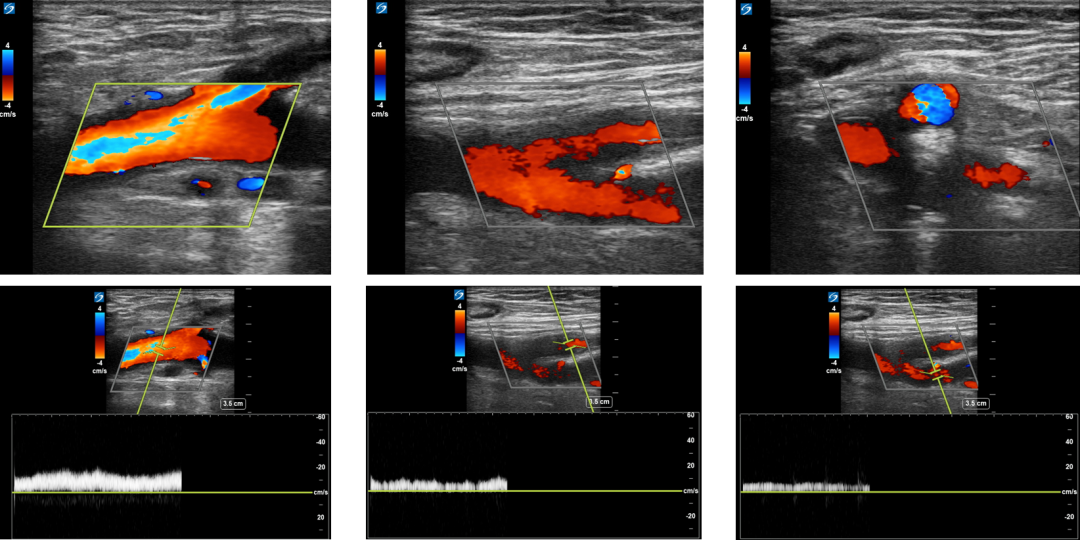

3月超声随访:左股总、股浅、股深静脉均通畅